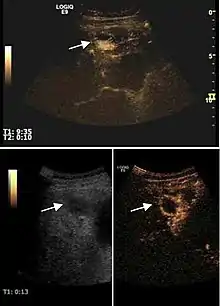

Ultrasound monitoring ablative therapies (alcoholization – PEI, radiofrequency ablation – RFA)

Ablative therapies are considered curative treatments for HCC together with surgical resection and liver transplantation and they are indicated for early tumor stages in patients with good liver function. Also they are successfully applied in the treatment of liver metastases, where surgical resection is contraindicated. They are chemical (intratumoral ethanol injection) or thermal (radiofrequency, laser or microwave ablation). They are applied in order to obtain a full therapeutic response, without affecting liver function. Complete response is locally proved by complete tumor necrosis with a safety margin around the tumor.

2D ultrasound, Doppler ultrasound and especially CEUS can play an important role in pretherapeutic staging, particularly when sectional imaging investigations (CT, MRI) provide uncertain results or are contraindicated. During the interventional procedure, ultrasound allows guidance of the needle into the tumor. CEUS allows guidance in areas of viable tissue and avoids intratumoral necrotic areas. CEUS also allows assessment of therapeutic effect immediately post-procedure (with the possibility of reintervention in case of partial response) . To accurately assess the effectiveness of treatment it is mandatory to compare the tumor diameter before therapy with the ablation area. The volume of damaged tissue must be higher than the initial tumor volume. CEUS appearance is that of central nonenhanced area showing a peripheral homogeneous hyperenhanced rim due to post-procedure inflammation. 24 hours after the procedure the inflammatory peripheral rim is thinning and the necrotic area appears larger than at the previous examination. Thus, a possible residual tumor may appear more evident. Residual tumor has poorly defined edges, irregular shape, and the tumor diameter is unchanged. Residual tumor tissue is evidenced at the periphery of the tumor as an eccentric area behaving as the original tumor at CEUS examination, with arterial hyperenhancement and portal and late wash-out. Ultrasound examination 24 hours after the procedure, including CEUS, can show apart from the character of the lesion any potential post-intervention complications (e.g. active bleeding).

In the first days after RFA both CEUS and spiral CT have low sensitivity in assessing therapeutic efficacy. CT sensitivity 24 hours post-therapy is reported to be even lower than CEUS. Difficulties in CEUS examination result from post-lesion hyperemia, presence of intratumoral air, ultrasound limitations (too deep lesion or the presence of fatty liver) or lack of patient's cooperation (immediately after therapy). For this reasons contrast imaging (CT or CEUS) control should be performed one month after ablation to confirm the result of the therapy.

Local recurrence is defined as recurrence of a hyperenhanced area at tumor periphery in the arterial phase, with portal and late wash-out. Sometimes, especially for HCC treated by alcoholization (PEI) hyperenhanced septa or vessels can be shown inside the lesion.